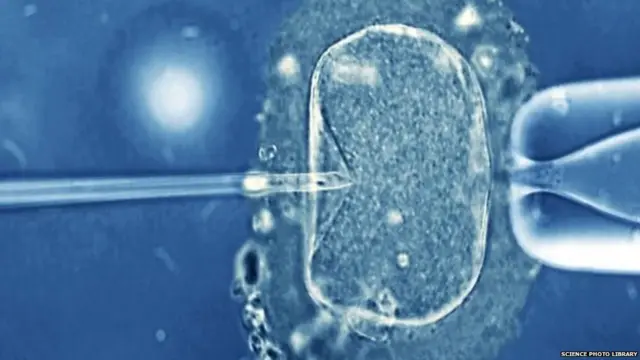

वो चाहते थे कि आईवीएफ़ तकनीक के ज़रिए उनका बच्चा इस दुनिया में आए.

इमेज स्रोत, Science Photo Library